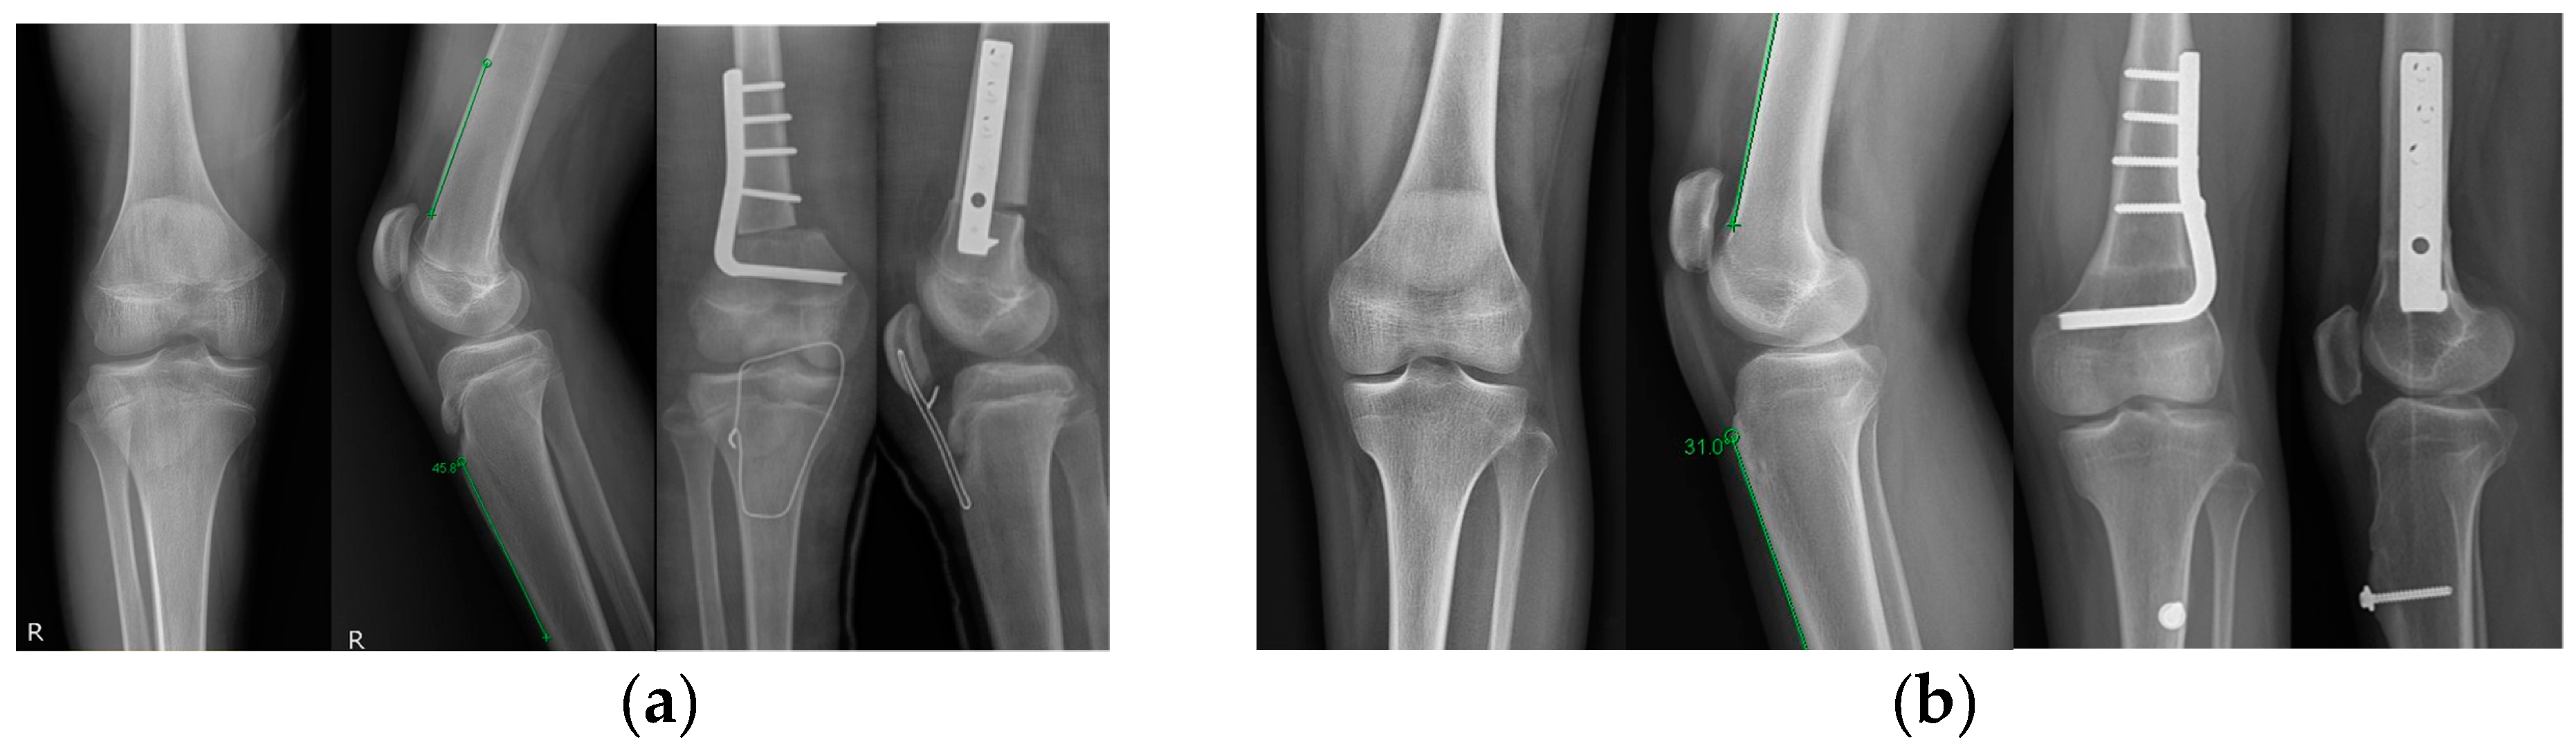

2.2. Surgical Technique